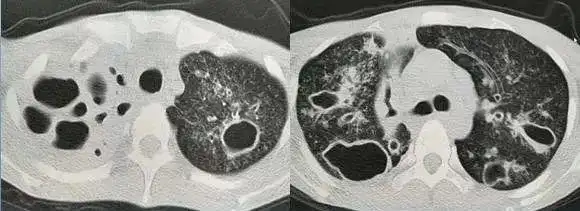

耐药肺结核治疗第14个月!

粟粒型肺结核

肺结核之烟花征——黄勇老师经典病例分享

肺结核如何诊断从胸部ct到实验室检查一文讲清世界防治结核病日